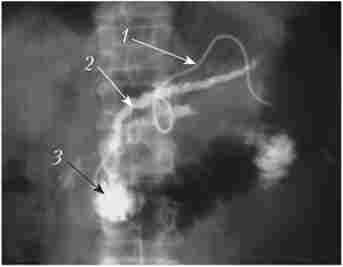

Черезшкірна пункція жовчних проток. Стрілками позначений кут, утворений голкою і правим печінковим протокою

Мал. 28.7. Черезшкірна пункція жовчних проток. Стрілками позначений кут, утворений голкою і правим печінковим протокою

Операція виконується під рентгенологічним контролем. Після проведення провідника в просвіт дванадцятипалої кишки по провіднику встановлюється або зовнішньо-внутрішній дренаж, або саморасправляю- щійся стент (рис. 28.8).

Зовнішньо-внутрішній ендопротезування пухлинної стриктури загальної жовчної протоки. Стрілками вказані відновлені ділянки

Мал. 28.8. Зовнішньо-внутрішній ендопротезування пухлинної стриктури загальної жовчної протоки. Стрілками вказані відновлені ділянки

жовчних проток:

а - дренування; б - стентування